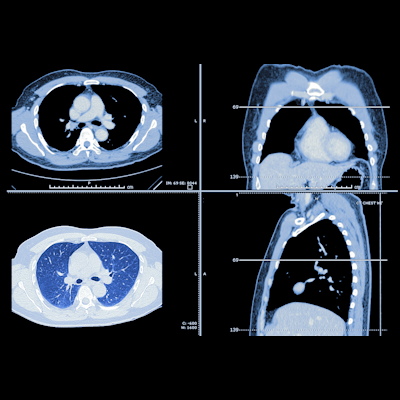

Aortic valve calcium scores have increasingly shown clinical utility as a prognostic risk factor in patients with aortic stenosis, but motion or blooming artifacts can affect the accuracy of manual segmentation. Therefore, it can often be challenging for radiologists to distinguish aortic valve calcium from surrounding structures. Furthermore, visual assessments of aortic valve calcium grade are subjective and often inaccurate, according to the authors.

As a result, they set out to create a deep-learning algorithm to provide fully automated quantification of aortic valve calcium from noncontrast-enhanced, electrocardiogram-gated cardiac CT exams. They also wanted to compare the performance of the algorithm's quantification of aortic valve calcium and Agatston score for classifying severe cases with that of visual gradings by radiologists.

The researchers trained and validated their algorithm using 452 scans and then tested it on a separate set of 137 cases. Each CT exam was manually annotated by a radiologist with seven years of experience in cardiothoracic imaging. In comparison with these manual measurements, the deep-learning algorithm yielded 99% sensitivity but 84.2% specificity for detecting aortic valve calcium.